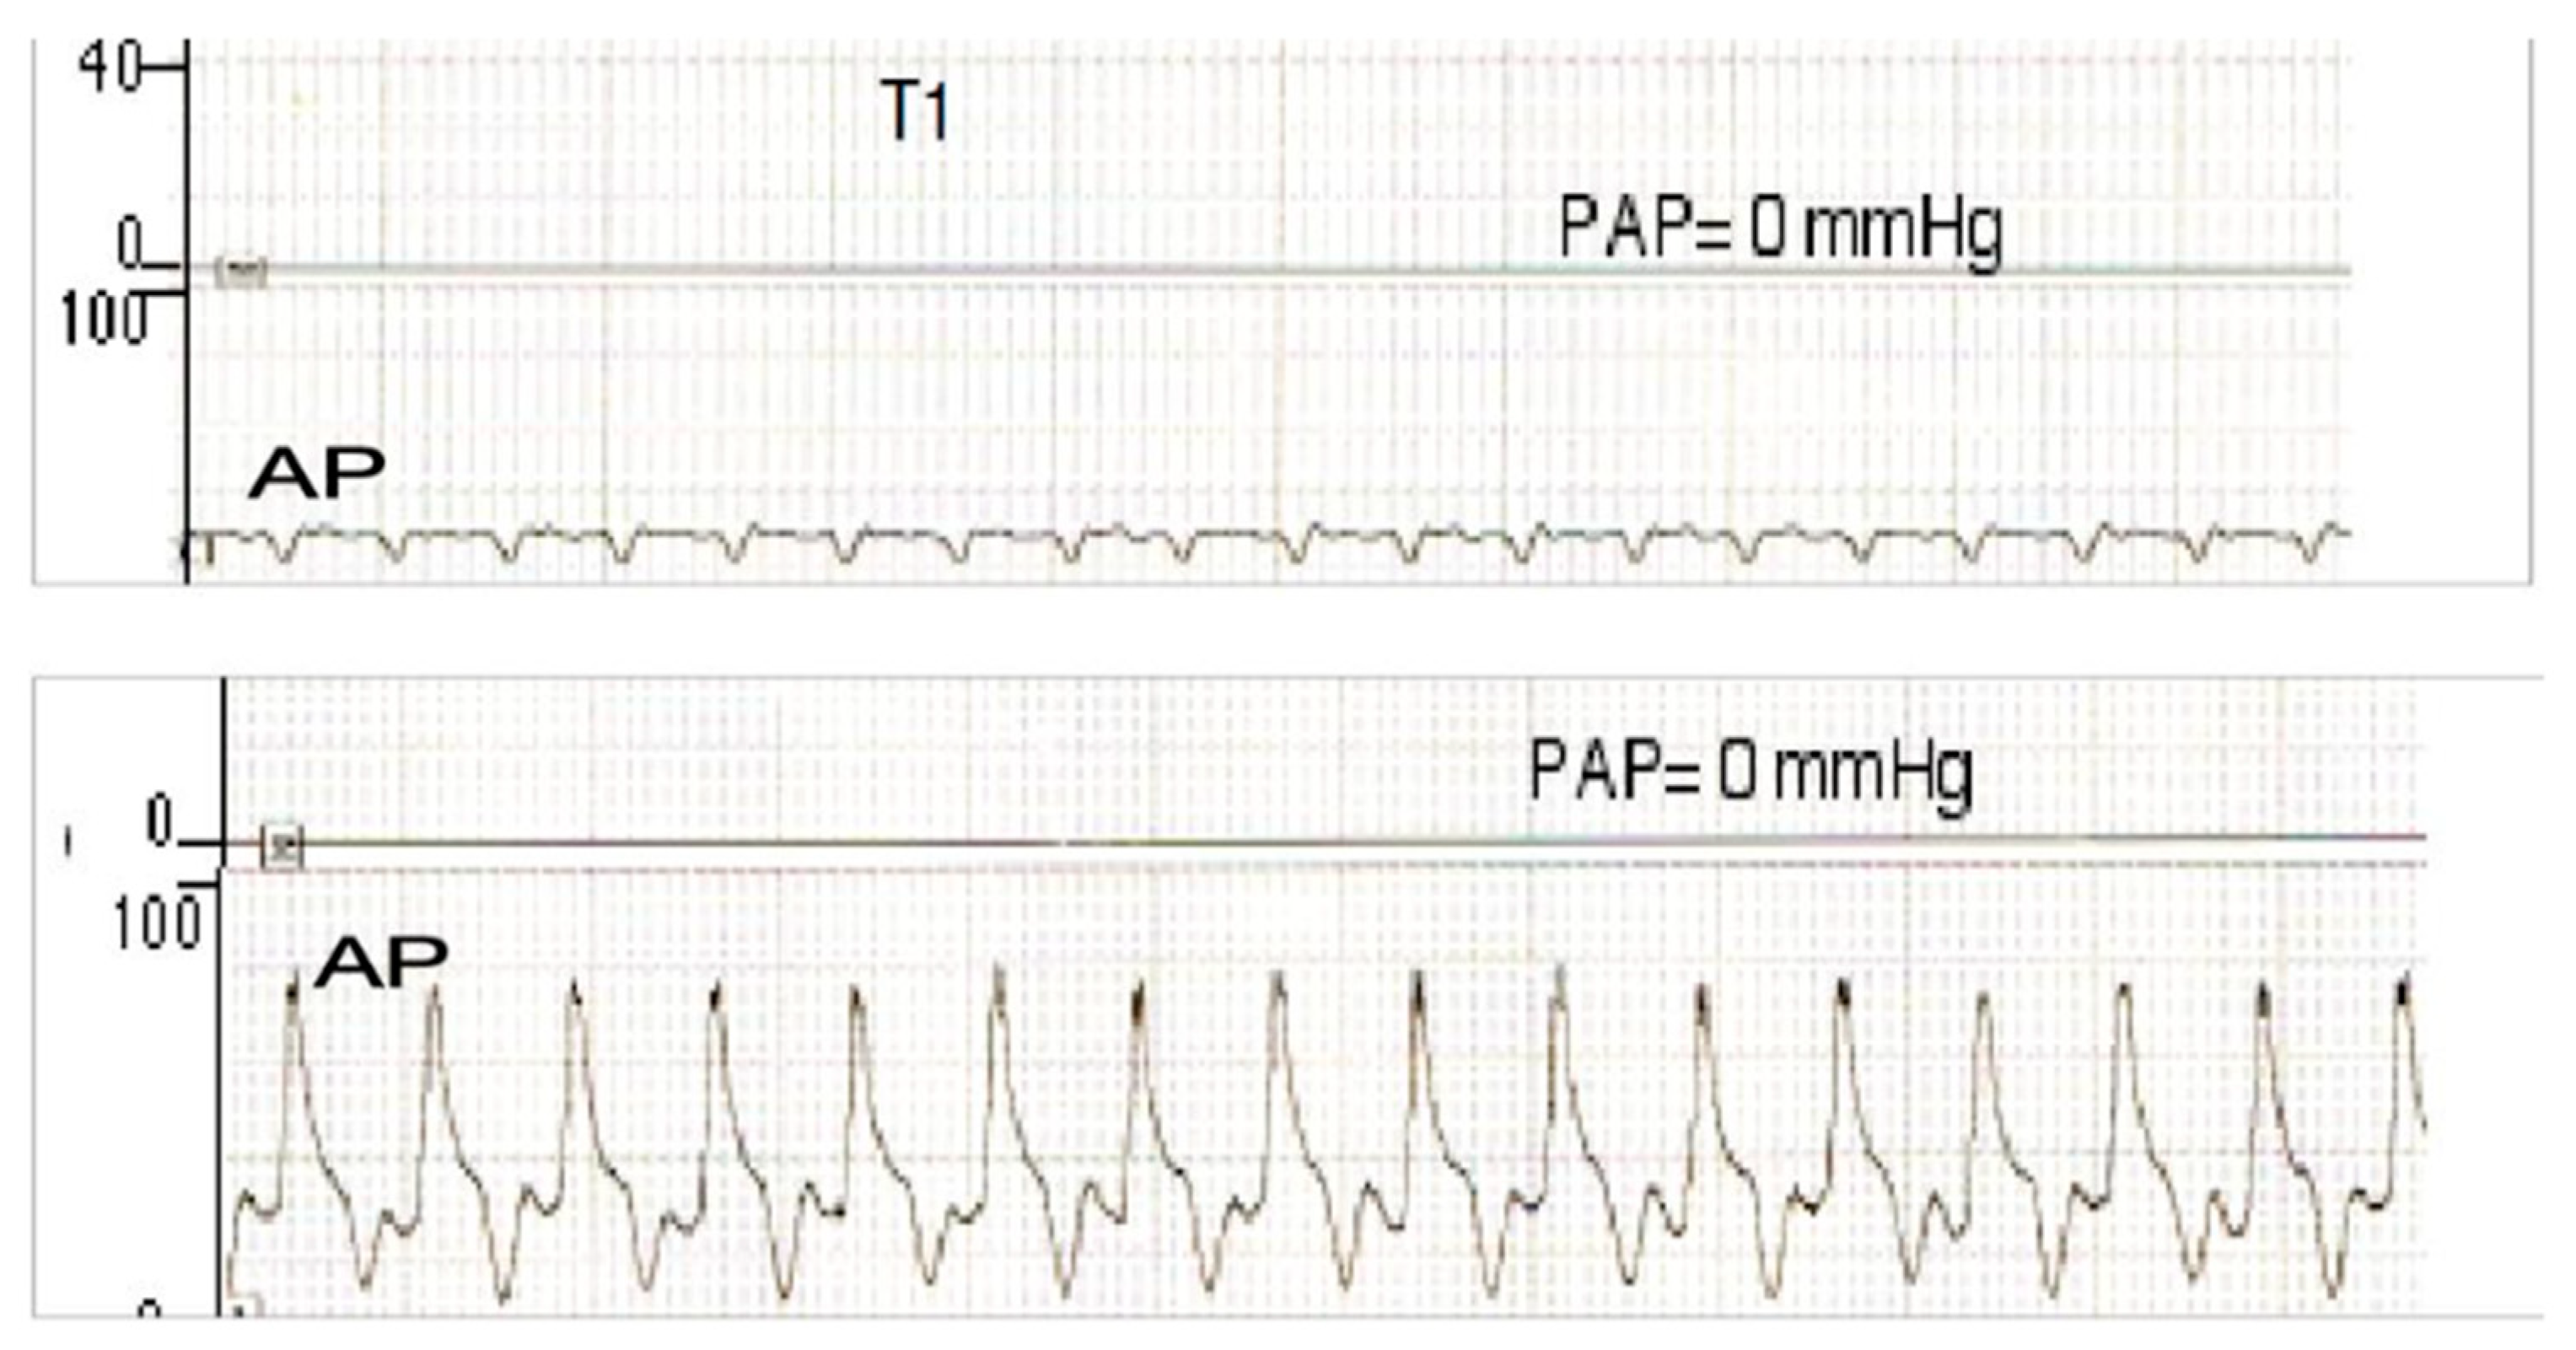

| AP | Arterial pressure |

| PAP | Pulmonary artery pressure |